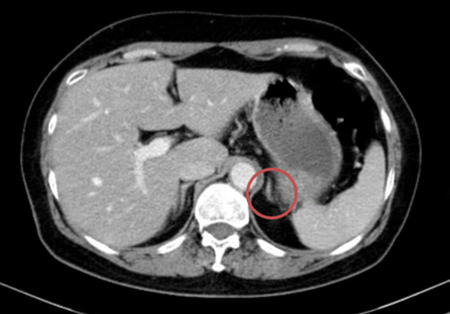

– Chụp cắt lớp vi tính bụng: Theo dõi dày khu trú tuyến thượng thận trái tạo nốt đường kính khoảng 9mm

Hình 3. Hình ảnh chụp CT bụng trước điều trị: Nốt tuyến thượng thận trái